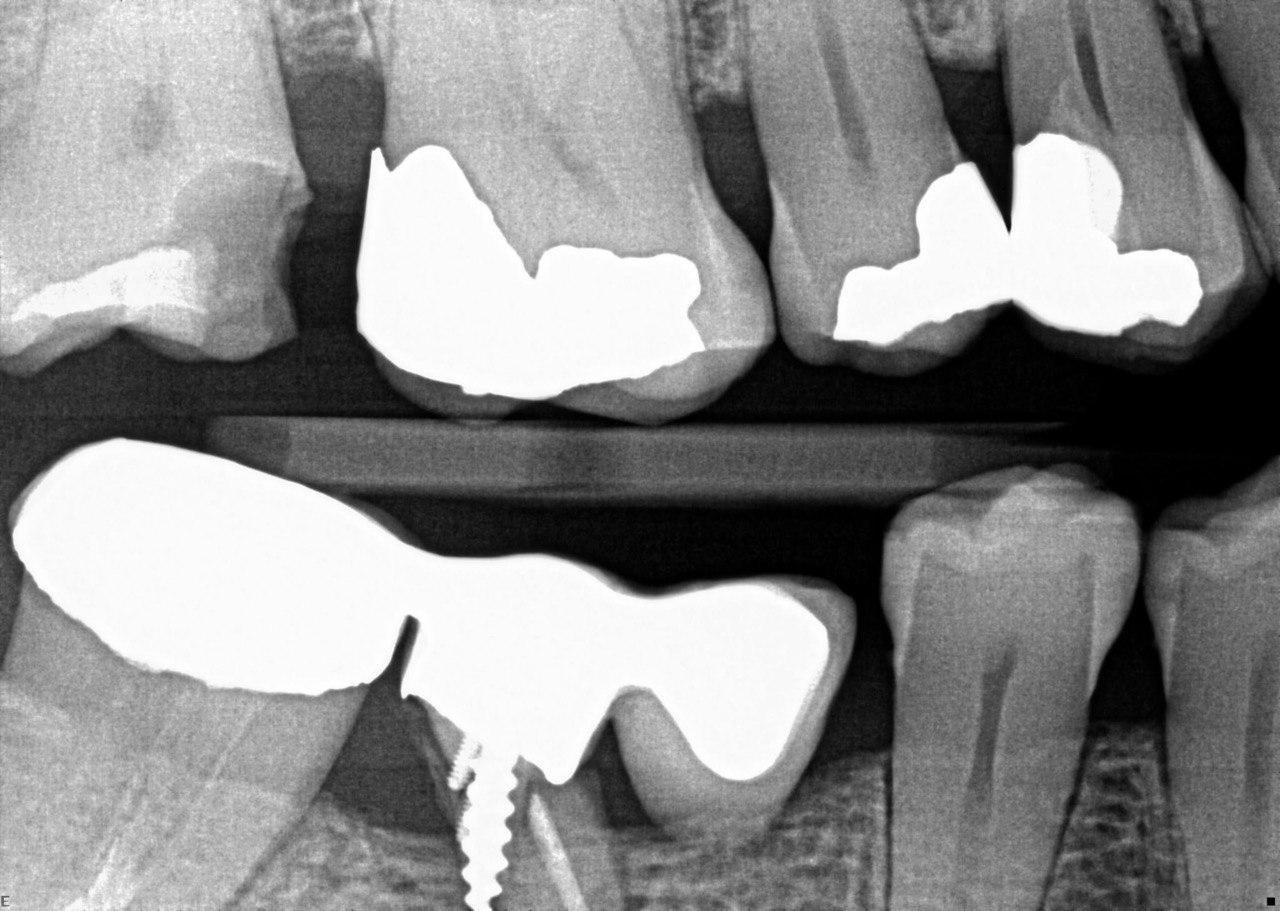

Question 21: What option is can be selected for distal tooth # 4.6?

Question 22: Which surface shows defective restoration?

Question 23: Which surface shows overhang?

Question 24: Which surface shows defective restoration?

Question 25: Which surface shows open margin?

Question 26: What option cannot be selected for mesial tooth surface # 2.8?

Question 27: What options cannot be seen in this X ray?

Question 28: What is the best option that describe distal surface of tooth # 3.5?

Question 29: What options cannot be seen in this X ray?

Question 30: What options can be selected for the tooth # 4.2?